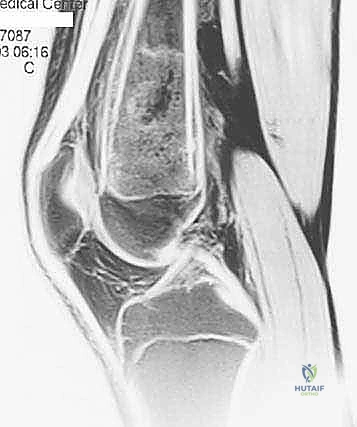

- الرنين المغناطيسي (MRI): هو المعيار الذهبي (Gold Standard) لتقييم الأورام. يوضح بدقة امتداد الورم في النخاع العظمي والأنسجة الرخوة، وعلاقته بالأعصاب والأوعية الدموية.

الحالة الأولى: إنقاذ ركبة رياضي شاب

شاب يبلغ من العمر 19 عاماً عانى من ألم مستمر في الركبة وتورم لم يستجب للمسكنات. بعد الفحص السريري الدقيق وإجراء الرنين المغناطيسي، اشتبه الأستاذ الدكتور محمد هطيف بوجود ورم. تم إجراء خزعة إبرة أساسية دقيقة جداً. أظهرت النتائج وجود "ساركوما عظمية" في مراحلها الأولى. بفضل الخزعة الدقيقة التي لم تلوث الأنسجة المحيطة، تمكن الدكتور هطيف لاحقاً من استئصال الورم بالكامل وتركيب مفصل صناعي خاص بالأورام، مما أنقذ ساق الشاب من البتر ومكنه من العودة للمشي بشكل طبيعي.